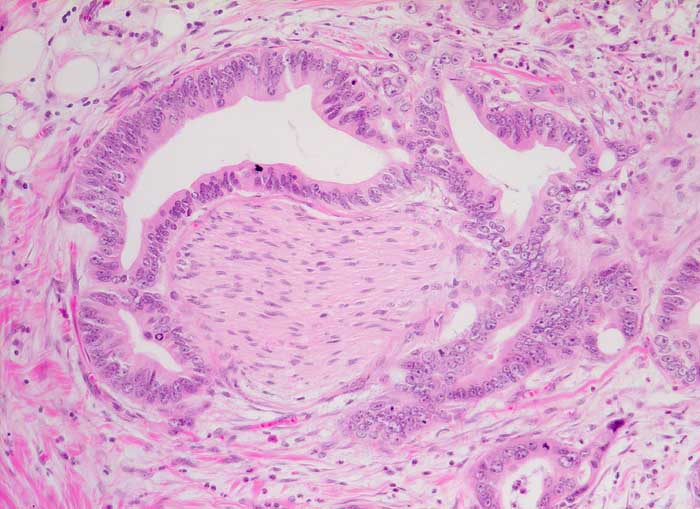

duktales Adenokarzinom des Pankreas: Nervenscheideninvasion

Drüsen mit deutlich atypischer Epithelauskleidung umschliessen konzentrisch einen peripheren Nerven.

Der Nachweis einer zirkulären Infiltration der Nervenscheiden durch atypische Drüsen bestätigt die Malignität des Tumors und ist vor allem unter Schnellschnittbedingungen ein hilfreiches Merkmal.